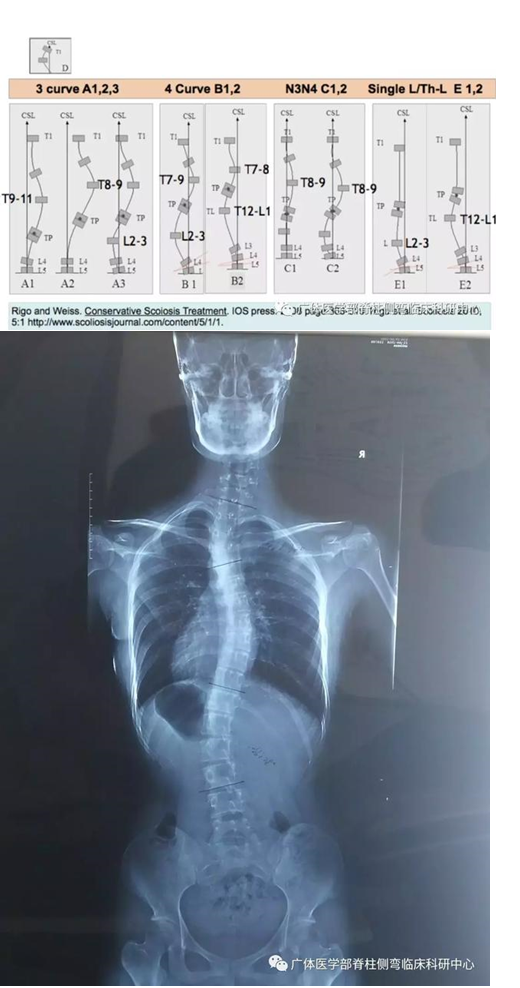

图9︰X片所示:RigoB1型(伴近胸弯),T1-T4左凸Cobb30°,T5-T11右凸Cobb29°;T11-L3左凸28°

图10所示:正常坐位三维超声测量:T1-T4左凸Scolioscan angle 26°,T5-T11右凸24°;T11-L3左凸25°,与站位X光片略有误差均为5°以内。叮嘱该同学特定的坐姿练习:模仿课堂中坐于课室左侧,「右抬头望月」观看幻灯片,保持右臀承重、躯干挺直体位

图11所示:三维超声测量度数(见下图):T1-T4左凸Scolioscan angle 16°,T5-T11右凸14°;T11-L3被矫正未测出度数。合并近胸弯的姿势矫正:改变承重,调整身体力线,保持双肩平衡的姿势体位,具有科学的依据